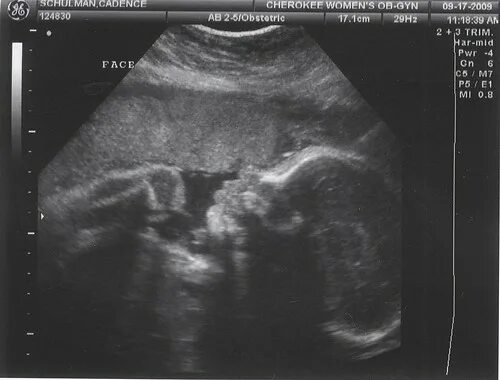

29 недель 4 дня